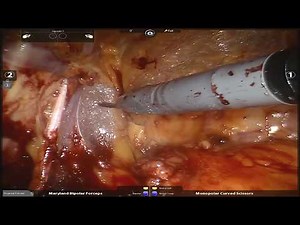

Robotic prostatectomy Full Case Step by Step with Expert Surgeon

This is a full case describing radical prostatectomy for prostate cancer. The patient has had a prior bilateral inguinal hernia repair with mesh, which has been a relative contraindication for robotic prostatectomy. This case was performed in 2014 with the DaVinci Si. The video is excellent for learning steps of robotic prostate surgery.